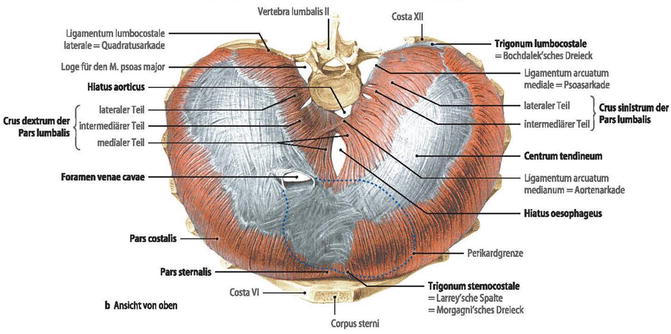

Анатомия диафрагмы и треугольника Бохдалека

Раздел: Визуальный дайджест